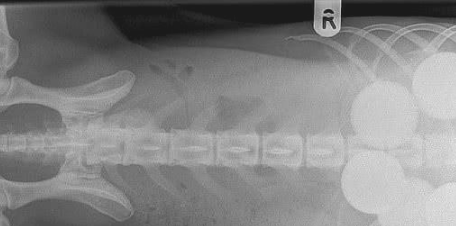

可是半天的時间过去,狗狗的腹部還是沒有消散,主人这才意识到,狗子应该是误吞了哪些东西进来,导致本身没法消化,因此将狗狗抱去医院体检,結果发觉了好多个环形的东西在肚里,但大夫在短期内内也没法鉴别是什么东西。

之后历经大夫长达2个多钟头的勤奋,总算将狗狗身体的环形物件排了出去,原先狗狗是误吞了五个高尔夫,导致没法消化,而高尔夫一般 全是由硬硫化橡胶或是塑胶等材料构成,更何况狗子也是全部吞进去的,因而消化不上也是一切正常的。